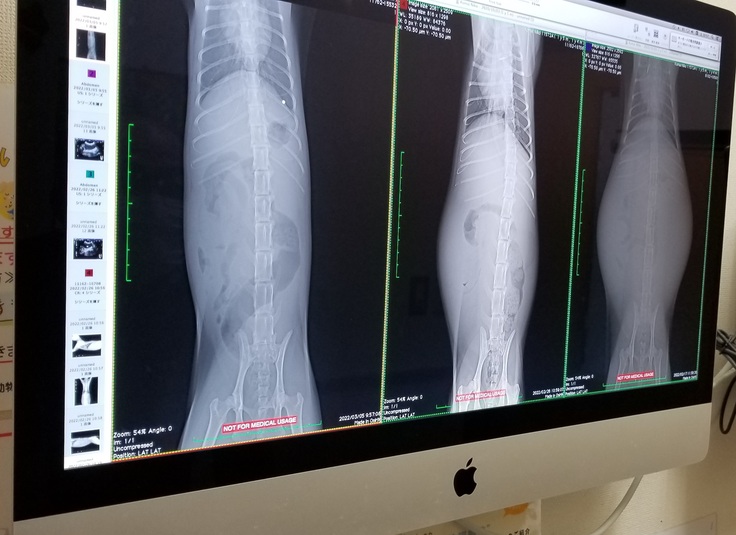

本日は3回目の検査日でした(3月5日)

1週間ぶりの病院で3回目の検査を行いました。

まだ血小板は少ないですが、赤血球、白血球ともに良好で

腹水もほぼ無くなり、元気になってきました。

左から3回目(3月5日)、2回目(2月26日)、1回目(2月17日)